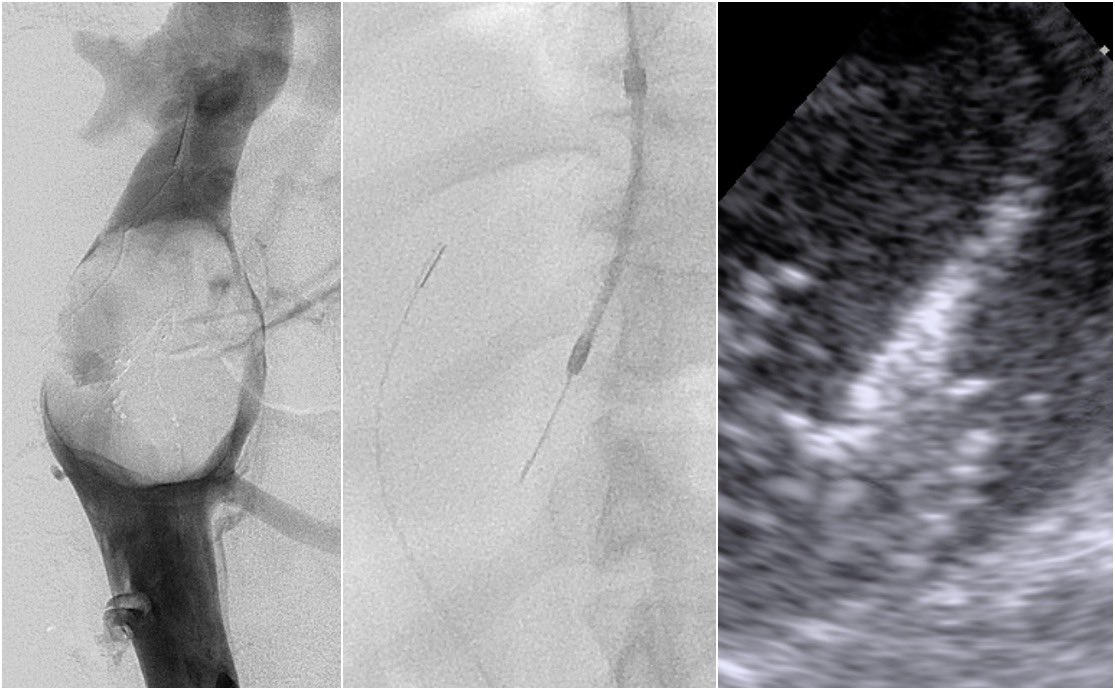

We are going Live! Hemorrhoid Embolization 9th October 2021 @12pm - *|jigglemed.com/live.html|*